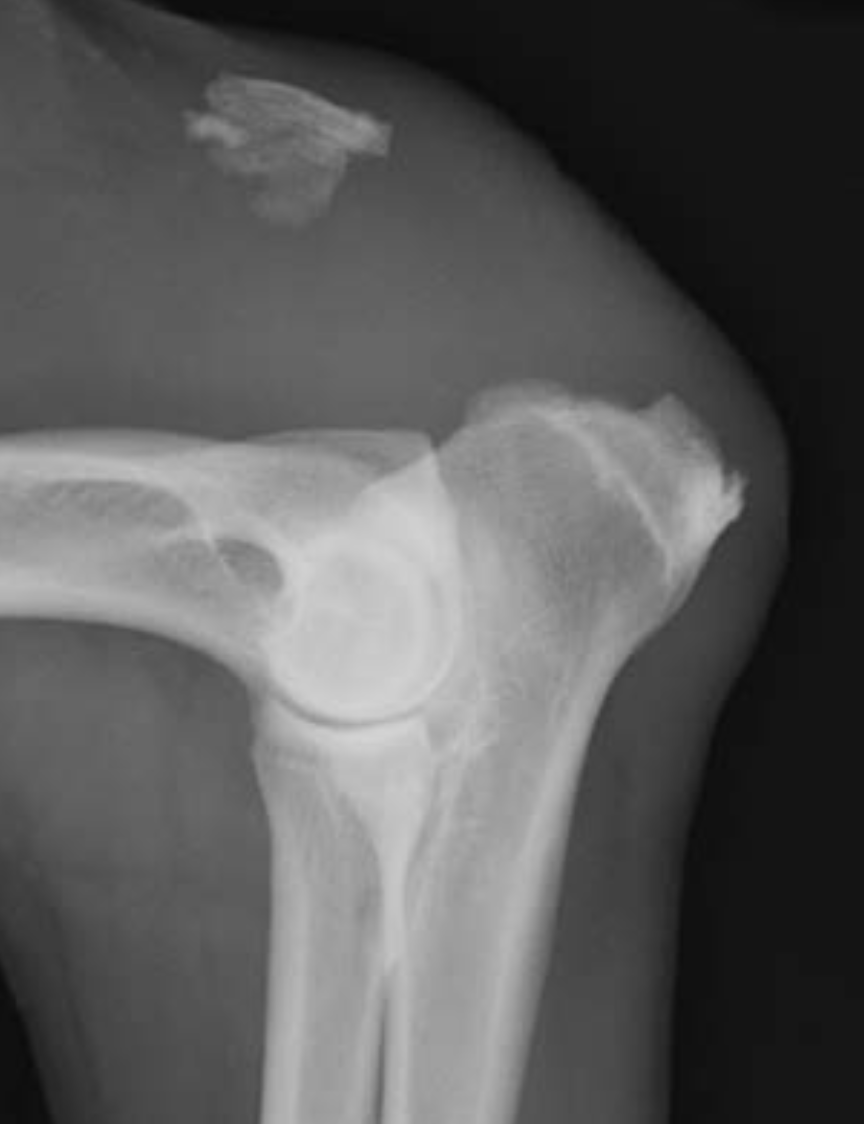

9

Q

3.5m Yorkie

A

lateral humeral condylar fracture - see its caudal displacement, superimposed over the cranial ulna.